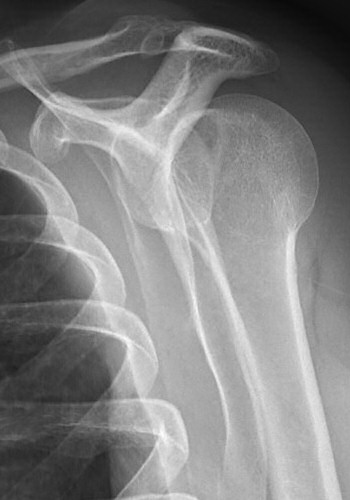

Bakre luxation, patienten hade mycket ont, kunde inte röra axeln alls. På frontalbilden ligger kaput roterat, på sidobild ligger kaput inte rätt i leden, på 3D-rekonstruktion syns felställningen tydligt (delar av nyckelben och akromion bortredigerade).